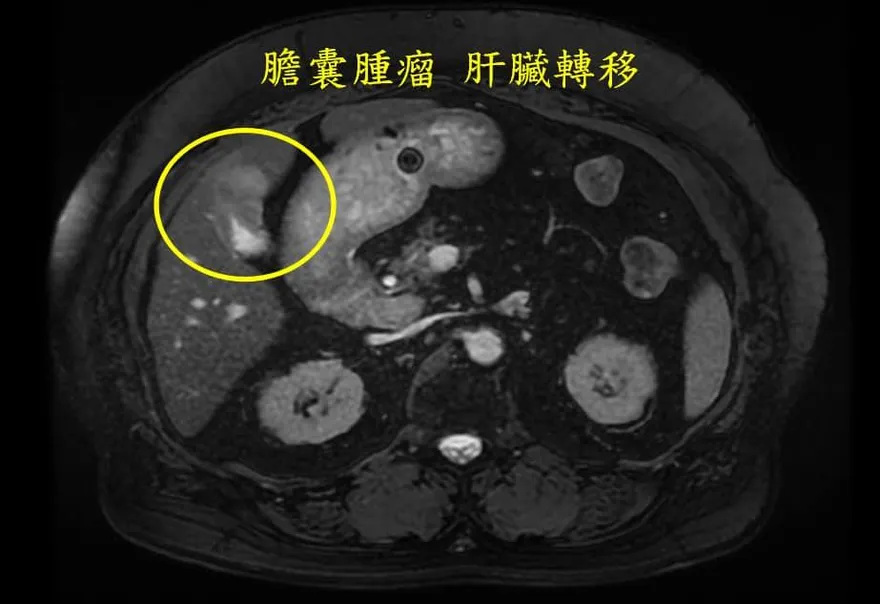

肝癌

腫瘤

膽囊癌

膽結石